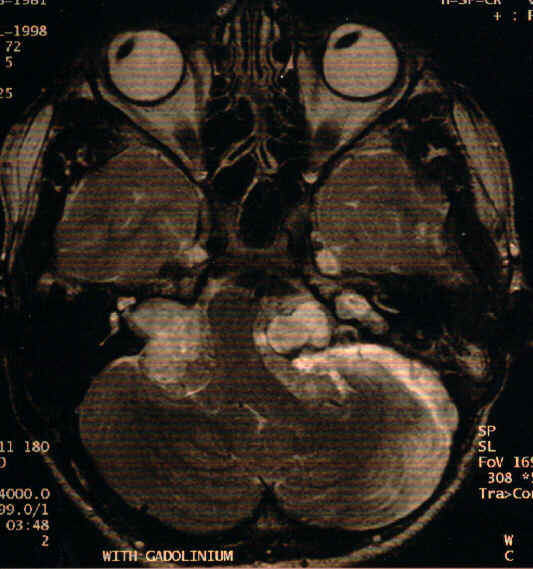

a. What abnormalities can be seen on this MRI scan and what is the most likely diagnosis?

b. What ocular signs may be present?

c. What inherited disease does he suffer from?